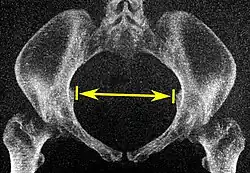

| Interspinous distance |

![]() Axial plane |

The line between the closest bone points of the ischial spines | 9.5 to 11.5 cm.[6] | |